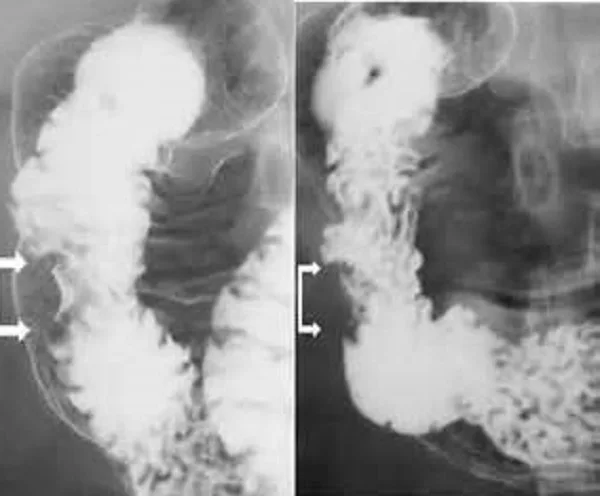

Señales del desarrollo de las hemorroides

¿Y saben a qué conduce todo esto? ¿Han visto las estadísticas de mortalidad en España? El año pasado, más de 66 000 personas murieron en nuestro país a causa de enfermedades del recto originadas por problemas relacionados con las hemorroides.

El verdadero problema es que las hemorroides provocan numerosas complicaciones: primero, diferentes fases de la propia enfermedad, luego inflamaciones, y finalmente cáncer colorrectal.

Cáncer de recto